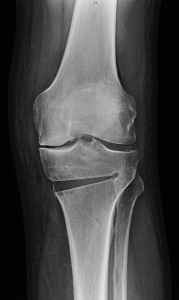

Lai noskaidrotu, vai šāda koriģējošā osteotomija būs pacientam piemērota, tiek veikti rentgenuzņēmumi, nosakot kāju varus/valgus leņķi, būtībā izsecinot, vai svars tiek vairāk nests uz ceļa iekšējās vai ārējās malas. Tiek uzskatīts, ka normāla kājas ass ir 5-7 grādi valgus pozīcijā, kad ceļgals ir nedaudz vērsts uz iekšu. Rentgens tiek veikts abām kājām visā to garumā, tajā tiek novilktas divas asis, mehāniskā un anatomiskā ass, kas norāda uz koriģējošo leņķi un ļauj pieņemt lēmumu kāda korekcija jāveic, lai pacients atgūtu anatomiski pareizu ceļa locītavas stāvokli.